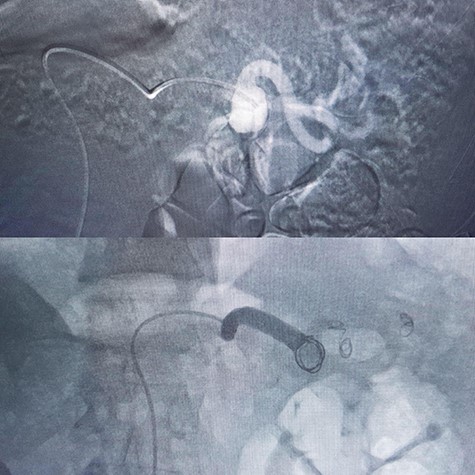

A 56-year-old male (fourth patient) evaluated for abdominal pain was referred to our hospital. In Computed tomography angiography (CTA) giant proximal SAA was diagnosed. We considered endovascular treatment. Angiography was carried out but because of arterial tortuosity wire did not pass through to the distal part of the artery. Hybrid surgery was the next plan. Balloon (7–40) expanded in proximal part of the aneurysm then in laparotomy, distal part was ligated and proximal part according to the inflated balloon was found easily (Fig. 1). After balloon was deflated, aneurysm was ligated and resected (Fig. 2).

Hybrid surgery: Aneurysm sac (Left), Angiography sheath and inflator (Right).

In a 52-year-old man (third patient), 3-cm SAA was found incidentally in ultrasound and CTA. According to size of the aneurysm, he was candidate for endovascular treatment. Angiography and positioning of the coils on either side of the aneurysm (‘sandwich technique’) was completed (Fig. 3). Post-embolization checks were performed with selective splenic, celiac and superior mesenteric artery angiograms to confirm occlusion of the main splenic artery and patency of the collateral arteries. All seven patients discharged with no procedure-related complications.